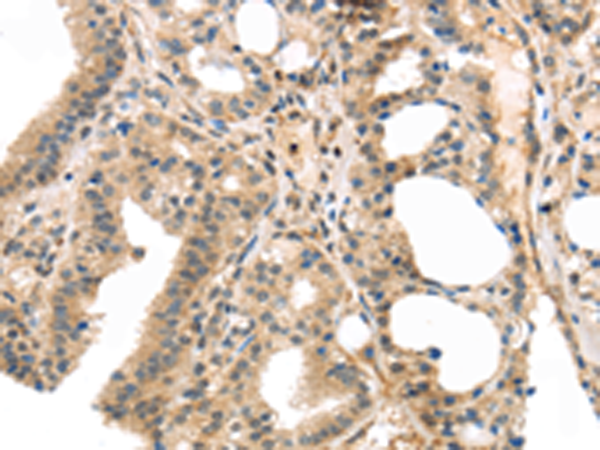

分类: 科研抗体货号: P10989别名: E170; LOCS; BM600; LAMNA应用: IHC反应种属: Human, Mouse